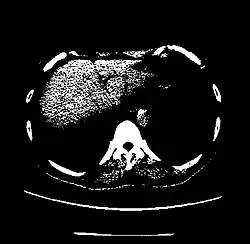

CT scan of the thorax with window level set to -700 HU (lung)

CT scan of the thorax with window level set to -1,000 HU (air)

CT scan of the thorax with window level set to 0 HU (water)

CT scan of the thorax with window level set to 60 HU (liver)